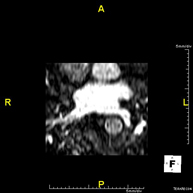

Prova diagnòstica no invasiva que consisteix en l'obtenció d'imatges d'alta definició anatòmica de la via biliar i de la vesícula biliar mitjançant l'ús d'un camp electromagnètic i ones de ràdio (amb un emissor i un receptor). No utilitza radiació ionitzant. És necessari realitzar un dejuni de 6 hores prèvies ja que, si no s'ha ingerit res, la bilis acumulada a la vesícula i a l'arbre biliar ens permetrà una millor definició anatòmica. Requereix l'obtenció de seqüències de Colangio-RM, que consisteixen en l'obtenció d'imatges de gruix molt fi (1 mm) i permet realitzar reconstruccions bidimensionals i tridimensionals sense la utilització de contrast paramagnètic (Gadolini). En algunes ocasions necessita l'ús de contrast paramagnètric (Gadolini) per caracteritzar les lesions. Està especialment indicada en pacients amb sospita de pedres a la vesícula, amb pedres a la vesícula amb sospita de desplaçament d'una de les pedres pels conductes biliars cap a l'intestí, pacients amb símptomes d'obstrucció de la via biliar, com a estudi pre-quirúrgic (mapa anatòmic de l'arbre biliar) abans de la cirurgia de la vesícula biliar, pacients amb dolor abdominal de probable origen biliar, etc. - Colangio-pancreàtic-RM (RM de Pàncrees, vesícula i via biliar)

Prova diagnòstica no invasiva que consisteix en l'obtenció d'imatges d'alta definició anatòmica dels conductes de drenatge pancreàtic (principalment el conducte de Wirsung), de la via biliar i de la vesícula biliar mitjançant l'ús d'un camp electromagnètic i ones de ràdio (amb un emissor i un receptor). No utilitza radiació ionitzant. És necessari 6 hores prèvies de dejuni ja que, si no s'ha ingerit res, la bilis i els sucs pancreàtics s'acumulen i permeten una millor definició anatòmica d'aquests. En algunes ocasions es requereix l'ús de contrast paramagnètric (Gadolini) per caracteritzar les lesions. Està especialment indicada en pacients amb sospita de pedres al conducte de drenatge de la via biliar o colèdoc, de malaltia a nivell de la unió dels conductes biliars i els pancreàtics, en pacients amb pancreatitis de repetició, dolor abdominal amb probable origen biliar o pancreàtic, com a estudi anatòmic pre-quirúrgic, etc. - RM de Pàncrees

Prova diagnòstica no invasiva que consisteix en l'obtenció d'imatges d'alta definició anatòmica del pàncrees mitjançant l'ús d'un camp electromagnètic i ones de ràdio (amb un emissor i un receptor). No utilitza radiació ionitzant. Requereix dejuni de 6 hores. Permet un estudi específic pancreàtic, tant de la part glandular com dels conductes de drenatge dels sucs pancreàtics, amb una alta definició tissular. També s'estudien els vasos pancreàtics i les estructures adjacents com són la vena porta, l'artèria i la vena esplènica, el greix peri-pancreàtic, l'aorta abdominal, la vena cava inferior, etc. En la majoria dels casos s'empra contrast paramagnètic (Gadolini) per a una millor definició tissular. Aquesta prova està especialment indicada en pacients amb sospita de lesions pancreàtiques, en pacients amb neoplàsia pancreàtica coneguda com l'estudi o mapa abans de la cirurgia, en pacients amb pancreatitis crònica o aguda, etc. - URO-RM